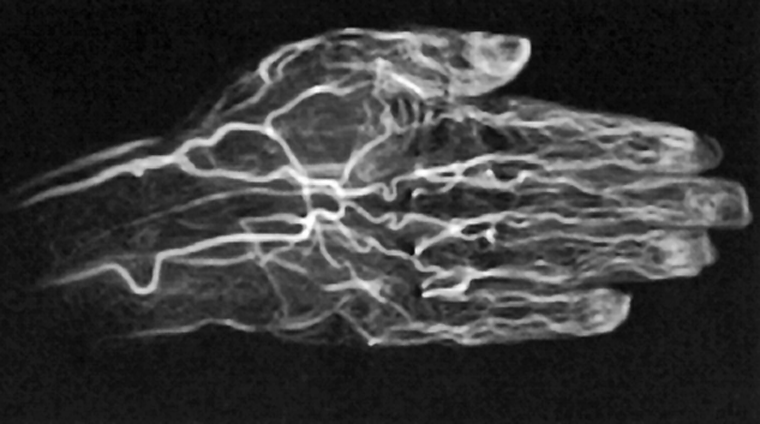

Figura 14-21:

CE TOF angiography of a hand.